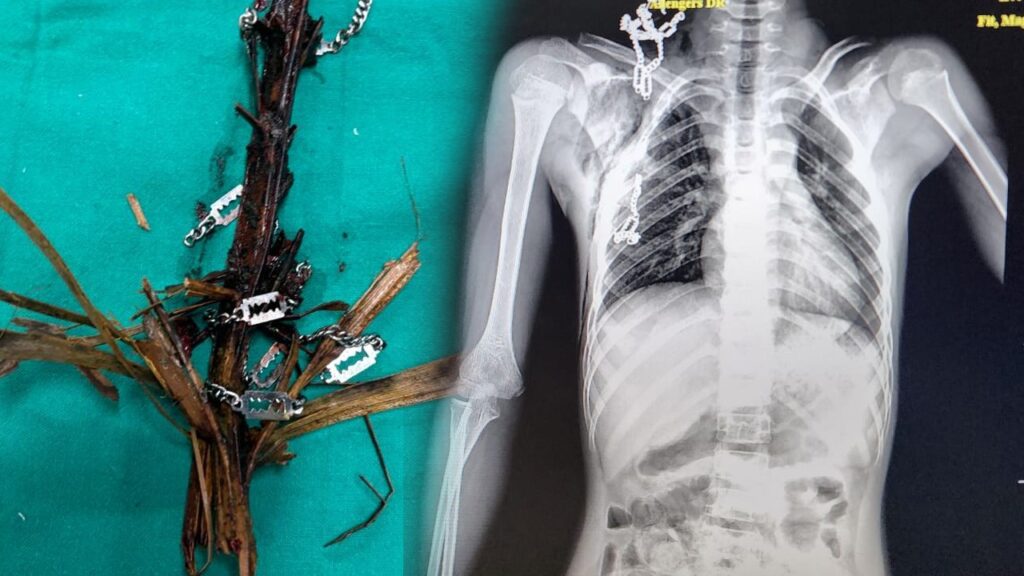

ಆಕಸ್ಮಿಕವಾಗಿ ಬಿದ್ದ ಬಾಲಕನಿಗೆ ಕುತ್ತಿಗೆಯ ಮೂಲಕ ಎದೆಯ ತನಕ ತೆಂಗಿನಗರಿಯ ಕೊಂಬೆಯ ಭಾಗವೊಂದು ಬಾಲಕನ ಕುತ್ತಿಗೆಯಲ್ಲಿ ಹಾಕಿಕೊಂಡಿದ್ದ ಸ್ಟೀಲ್ ಚೈನ್ನೊಂದಿಗೆ ಎದೆಯ ಒಳಗಡೆಗೆ ಹೊಕ್ಕಿತ್ತು. ಮಡಿಕೇರಿಯ ಸರ್ಕಾರಿ ಆಸ್ಪತ್ರೆಯಲ್ಲಿ ಹುಡುಗನಿಗೆ ಪ್ರಾಥಮಿಕ ಚಿಕಿತ್ಸೆಯ ಬಳಿಕ ಕೂಡಲೇ ಮಂಗಳೂರಿನ ವೆನ್ಲಾಕ್ ಆಸ್ಪತ್ರೆಗೆ ಕರೆತರಲಾಗಿತ್ತು. ಹೊಕ್ಕಿದ್ದ ತೆಂಗಿನಗರಿಯನ್ನು ಸುದೀರ್ಘ ಗಂಟೆಗಳ ಶಸ್ತ್ರಚಿಕಿತ್ಸೆ ನಡೆಸಿ ಮಂಗಳೂರು ನಗರದ ಸರಕಾರಿ ವೆನ್ಲಾಕ್ ಆಸ್ಪತ್ರೆಯ ವೈದ್ಯರು ಬಾಲಕನ ಜೀವ ಉಳಿಸುವಲ್ಲಿ ಯಶಸ್ಸು ಕಂಡಿದ್ದಾರೆ.

ಅಸ್ಸಾಂ ರಾಜ್ಯದ ಗುವಾಹಟಿ ಮೂಲದವನಾದ ಬಾಲಕ ಕಮಲ್ ಹುಸೇನ್(12) ಎಂಬಾತನ ಪೋಷಕರು ಕೊಡಗು ಜಿಲ್ಲೆಯ ಮಡಿಕೇರಿಯ ಕಾಫಿ ಎಸ್ಟೇಟ್ ಒಂದರಲ್ಲಿ ಕೂಲಿ ಕೆಲಸ ಮಾಡುತ್ತಿದ್ದಾರೆ. ನಿನ್ನೆ ಸಂಜೆಯ ಬಾಲಕ ಮನೆಯ ಬಳಿ ಆಟವಾಡುತ್ತಿದ್ದಾಗ ಹತ್ತಿರವೇ ಇದ್ದ ತೆಂಗಿನಮರದ ಗರಿಯೊಂದು ಬಾಲಕನ ಮೇಲೆ ಬಿದ್ದು ಅವಘಡ ಸಂಭವಿಸಿತ್ತು. ಈ ಪ್ರಕರಣವನ್ನು ಕೂಡಲೇ ಗಂಭೀರವಾಗಿ ಪರಿಗಣಿಸಿದ ವೆನ್ಲಾಕ್ ಆಸ್ಪತ್ರೆಯ ಎದೆ ಮತ್ತು ರಕ್ತನಾಳಗಳ ಶಸ್ತ್ರಚಿಕಿತ್ಸಕರಾದ ವೈದ್ಯರಾದ ಡಾ. ಸುರೇಶ್ ಪೈ ನೇತೃತ್ವದ ತಂಡವು, ತಮ್ಮ ವೈದ್ಯಕೀಯ ಕೌಶಲ್ಯದ ಮೂಲಕ 12 ವರ್ಷದ ಹುಡುಗನ ಎದೆಗೆ ಹೊಕ್ಕಿದ್ದ ತೆಂಗಿನ ಮರದ ತುಂಡಿನೊಂದಿಗೆ ಎದೆಗೆ ಹೊಕ್ಕಿದ್ದ ಸ್ಟೀಲ್ ಚೈನ್ ನ್ನು ಯಶಸ್ವಿಯಾಗಿ ಹೊರತೆಗೆದಿದ್ದಾರೆ.

ಮಧ್ಯರಾತ್ರಿ 1.30 ರಿಂದ 3.30 ರವರೆಗೆ ಶಸ್ತ್ರಚಿಕಿತ್ಸೆ ನಡೆಯಿತು. ಶಸ್ತ್ರಚಿಕಿತ್ಸೆ ಸಕ್ಸಸ್ ಆಗಿದ್ದು ಬಾಲಕ ಚೇತರಿಸಿಕೊಳ್ಳುತ್ತಿದ್ದಾನೆ. ಸರಕಾರಿ ಆಸ್ಪತ್ರೆಯಲ್ಲೂ ಕ್ಲಿಷ್ಟಕರವಾದ ಶಸ್ತ್ರಚಿಕಿತ್ಸೆ ಕೂಡ ಮಾಡಬಹುದು ಎಂದು ತೋರಿಸಿ ಕೊಟ್ಟಿದ್ದಾರೆ.